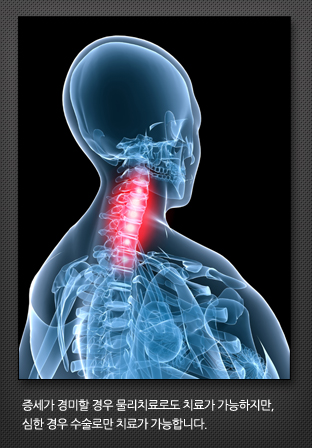

목 디스크

목뼈 사이에 디스크라는 연골조직이 있는데 이 디스크가 튀어나와서 목, 어깨, 팔로 가는 신경조직을 누르기 때문에 통증이 발생합니다.목 디스크가 있는 경우 목도 아프지만 실제로는 어깨관절 주변과 팔로 저려 내려오는 통증이 주된 증상입니다.증상이 경미한 경우 물리치료로 호전이 되나 통증이 심하거나 마비 증상이 있을시에는 수술적인 치료를 선택하게 됩니다.목디스크는 다른 말로 경추추간판탈출증 [頸椎椎間板脫出症, ruptured cervical disk] 라는 병명을 가지고 있기도 하듯이 목부분의 통증을 수반하며 근육 강직이 일어나는데 이러한 증상이 나타났다 사라지기를 반복하고 어깨에서 가슴쪽으로 전해지는데 경추 사이의 추간판이 튀어나와서 신경을 자극합니다.여기에서

연성추간판(soft disc)과 경성추간판(soft disc)으로 나눌수 있습니다.경추 뒤쪽에서 군더더기 뼈가 자라서 신경을 자극하는 경성추간판(hard disc)은 대부분의 환자들이 50대 이상이며 남성이 여성보다 약 3배 정도 많고 과거에 목에 충격을 받은 경험이 있는 경우가 많습니다.

증세가 경미할 경우 물리치료로도 치료가 가능하지만, 심한 경우 수술로만 치료가 가능합니다.